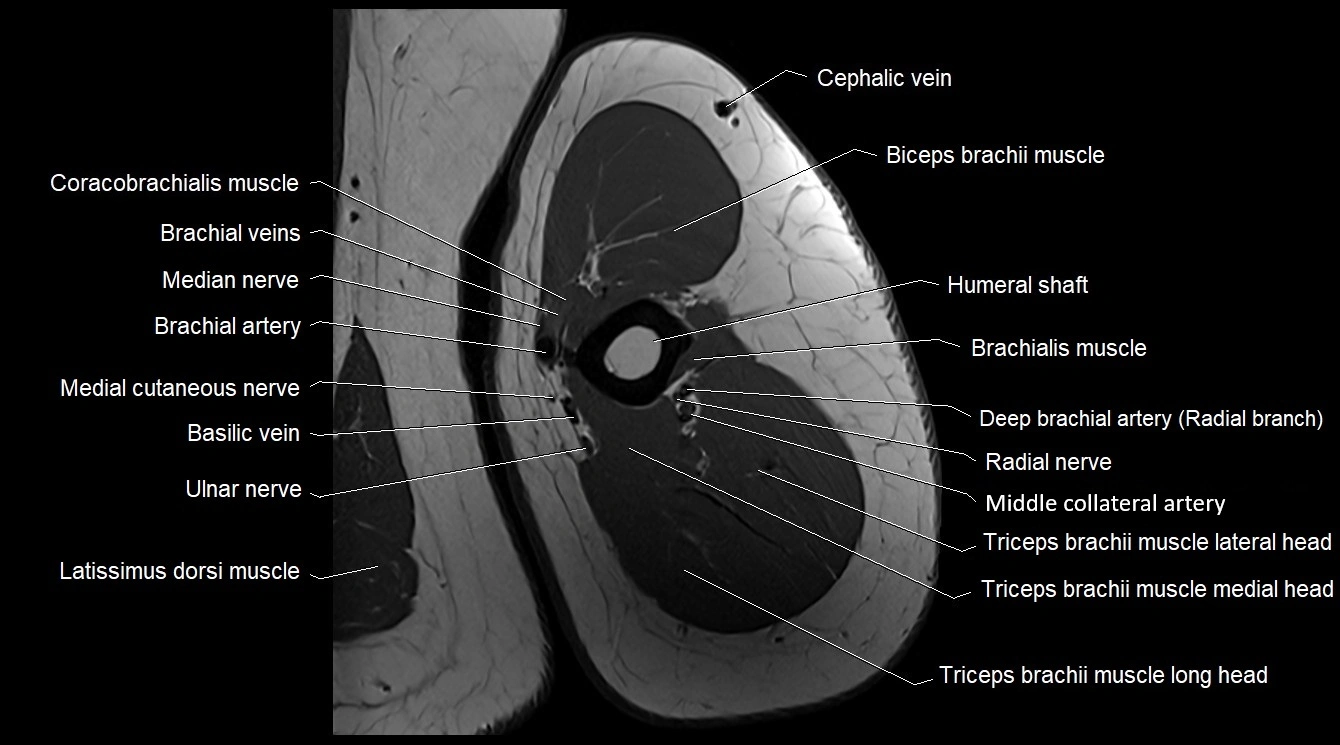

- Biceps brachii muscle

- Brachial artery

- Brachialis muscle

- Cephalic vein

- Coracobrachialis muscle

- Lateral head of triceps brachii muscle

- Latissimus dorsi tendon

- Long head of triceps brachii muscle

- Medial cutaneous nerve of forearm

- Medial head of triceps brachii muscle

- Median nerve

- Middle collateral artery

- Radial nerve

- Triceps brachii muscle